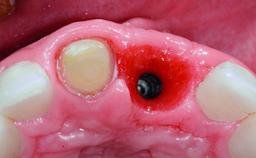

Replacement of an Upper Right Central Incisor with Root Resorption: Ridge Preservation, Delayed Placement of an NC Bone Level Roxolid Implant

A 32-year-old female Caucasian patient with a compromised maxillary right central incisor was referred to us by a general dentist. Her chief complaints were discomfort and mobility of tooth 11 with unsatisfactory esthetics due to discoloration. The patient reported a previous trauma, some years earlier, as the origin of pathology on the afflicted tooth. Anamnesis was negative for any other dental or periodontal pathology in the remaining dentition. The patient did not take any medication and reported to be a light smoker (5–10 cigs/day). She had high esthetic expectations of her treatment. The extraoral examination revealed a high smile line with full exposure of her maxillary teeth and surrounding soft tissue in the area between the second premolars.